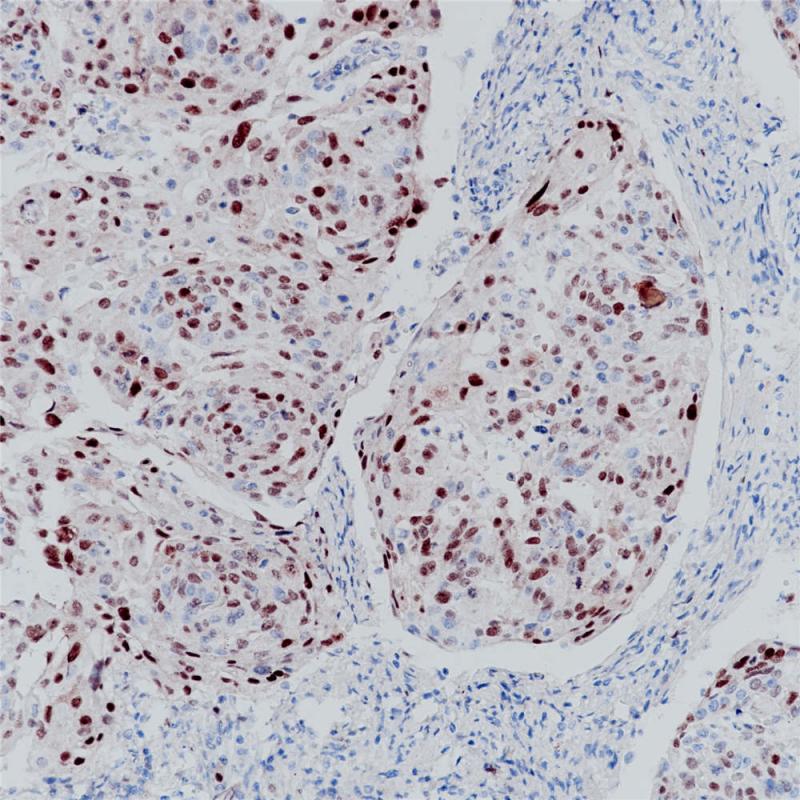

MUM1是由多发性骨髓瘤基因(Multiple Myeloma Oncogene1或IRF4)编码的一种50kDa的蛋白。MUM1蛋白表达形态谱范围是从中心细胞到浆母细胞,在B细胞分化晚期呈过度表达。该抗体与BCL6和CD138抗体联合使用,能够帮助更好的了解B细胞淋巴瘤组织发生的机制与过程。MUM1与CD30的抗体组合是经典型何杰金氏淋巴瘤RS细胞的最好标记物。此外,MUM1表达与肿瘤预后相关。

阳性对照

弥漫性大B细胞淋巴瘤

亚细胞定位

细胞核